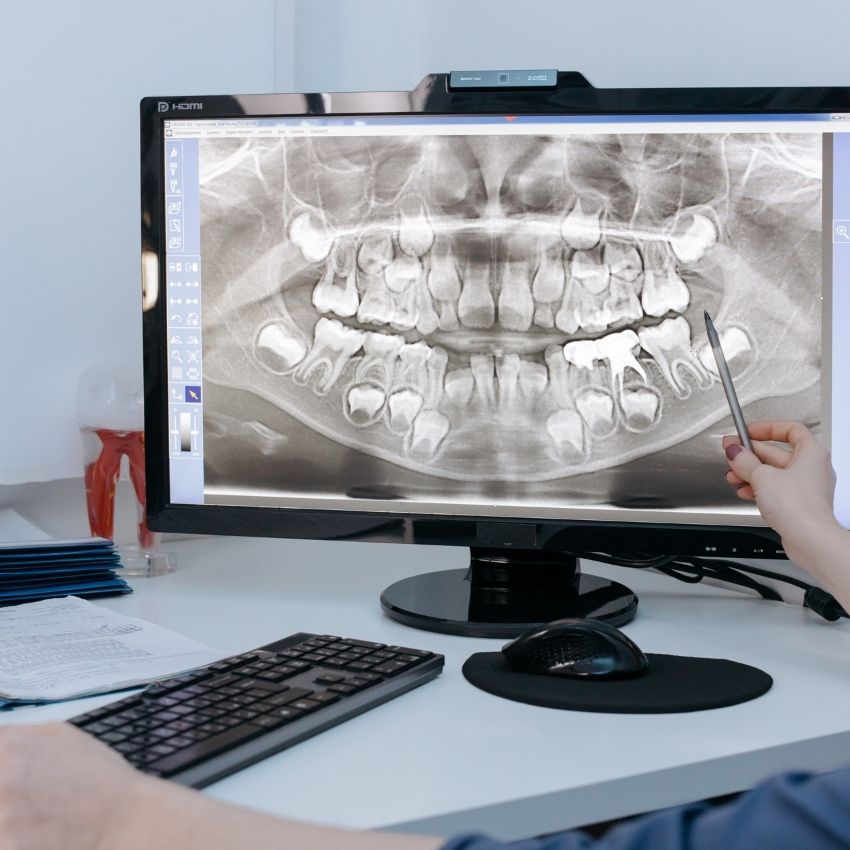

Nuestros doctores realizan un examen completo y revisan cada diente. Te preguntaremos a cerca del resultado que vienes buscando con respecto a tu salud bucal y pondremos solución a cualquier problema que detectemos. Una vez completado el análisis inicial, nuestros dentistas te hablarán sobre tu salud bucal y las necesidades aplicables a tu caso.